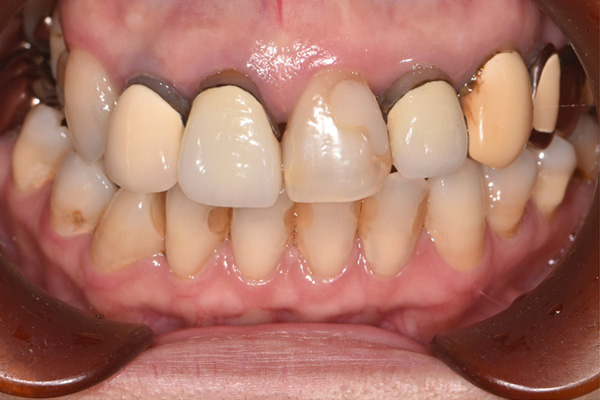

| 年代・性別 | 50代 男性 |

|---|---|

| 主訴 | 右上下の歯が痛い |

| 治療期間 | 約12ヶ月 |

| 費用 | 2,500,000円 |

| 治療内容 | インプラント、骨造成、結合組織移植、セラミック修復 |

| 治療に伴うリスク | インプラント周囲炎 セラミックの破折、脱離 |

*キャンセルポリシーをご一読のうえご予約ください